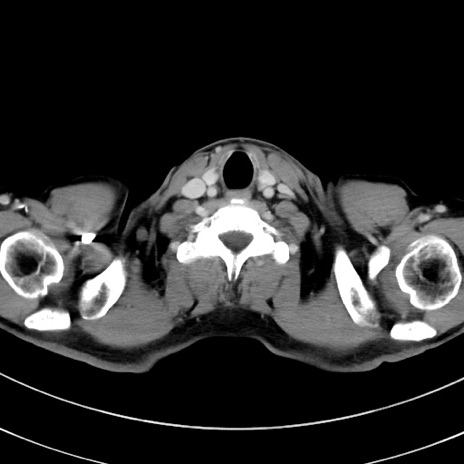

症例8(横断像)

【症例】 60歳代男性

【主訴】 黒色吐物

【現病歴】 4日前から嘔気自覚、2日前の朝食後にも嘔気あり、自分で手で嘔吐反射起こし嘔吐したところ血が混ざっていたため受診。

【既往歴】 5年前汎発性腹膜炎を伴う急性虫垂炎で手術、高血圧、前立腺肥大症、高脂血症

【身体所見】 腹部正中に手術癩痕あり 腹部平坦・軟圧痛なし膨満感あり

【データ】WBC 8400、CRP 4.54